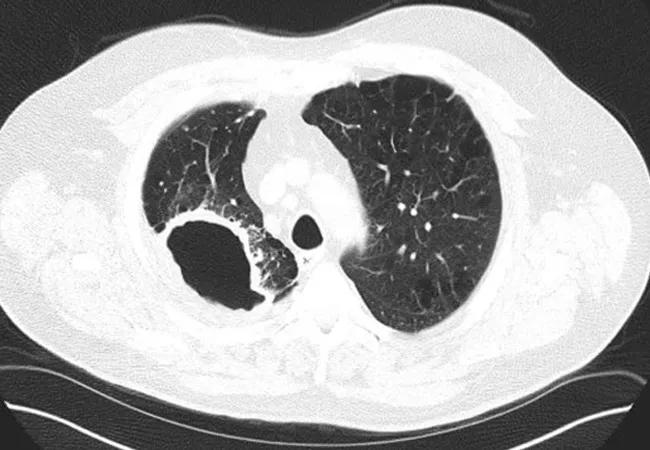

The prevalence of MAC lung disease in the U.S. has increased significantly in the past 10-15 years as providers have become more aware of the disease and more likely to detect it through sputum culture or bronchoscopy as follow-up to an abnormal CT scan of the chest, notes Dr. Dasenbrook. MAC is the most common type of nontuberculous mycobacterial infection.